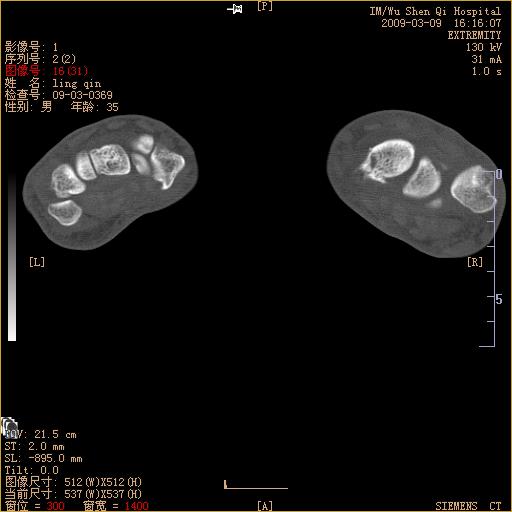

腕部有骨折、脱位,骨科面对ct片如何采取措施?三维一下。

x光片有时骨折看不出,ct看得出多骨骨折,我碰到几例,挺忽悠人的

左侧舟骨及桡骨茎突骨折,第一掌骨基底部好像也有骨折,建议上传平片